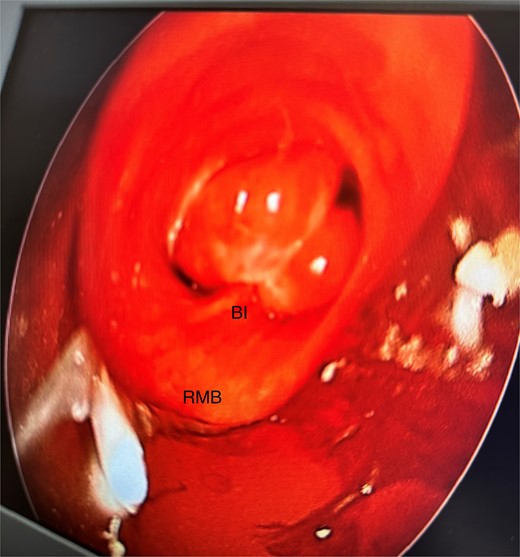

She initially underwent a rigid bronchoscopy, biopsy of the endobronchial tumour, cryoablation, and argon plasma for debulking. On direct visualization with the telescope the tumour was polypoid and was arising from the membranous portion of the right main bronchus (RMB) (Fig. 2).

Initial rigid bronchoscopy showing a polypoid mass originating from the membranous portion of the right main bronchus; BI, bronchus intermedius; RMB, right main bronchus.